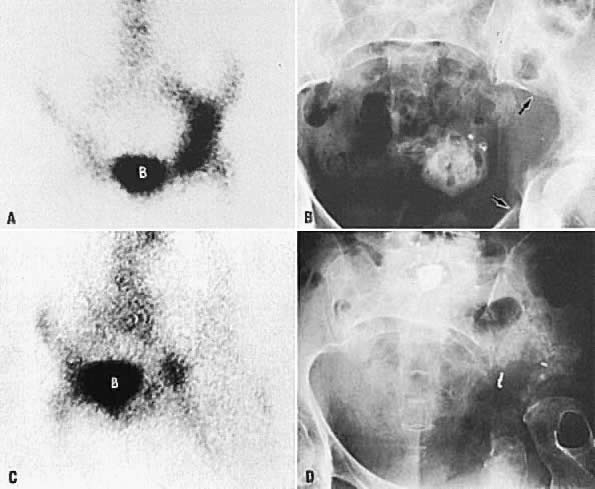

A. Bone scan shows increased radioisotope uptake in left acetabulum and ilium. B. Radiograph of pelvis shows destruction and some osteoblastic activity in left ilium and acetabular area (between arrows ). C. Bone scan 14 months after A and B shows less activity on the left than is shown in A. Osteoblastic activity at this time is much less than previously shown in A. D. Radiograph demonstrates much larger lytic areas than in B. Acetabulum and adjacent bony areas are completely destroyed. Femur is rotated, but femoral head is intact. (B, bladder.)